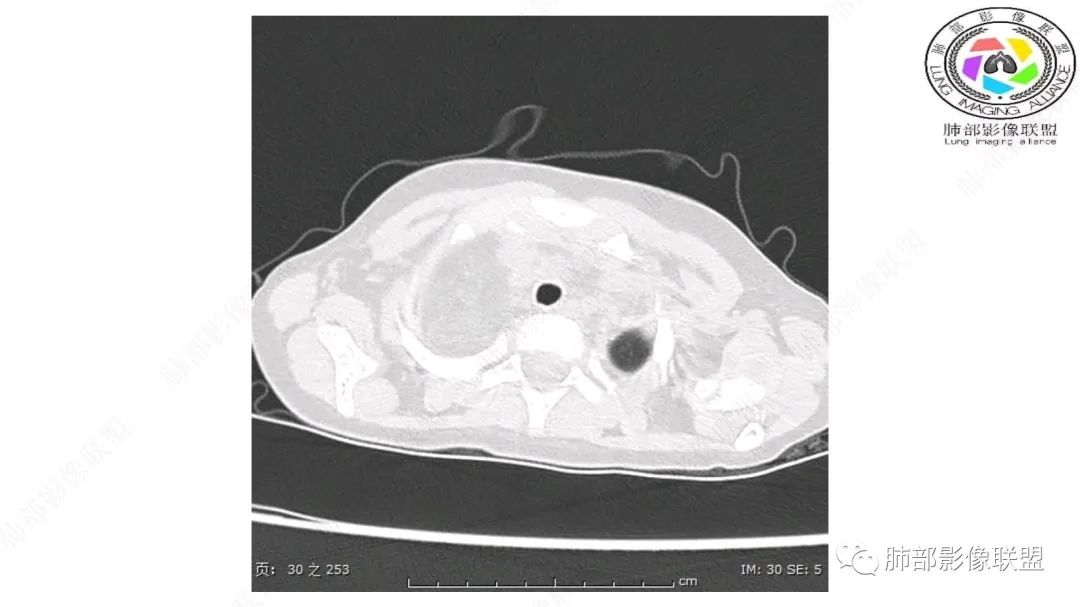

患儿3岁 咳嗽检查发现纵隔占位。右肺上叶受压表现,占位以脂肪组织密度为主,似见分隔,首先考虑为脂肪母细胞瘤,鉴别脂肪瘤,畸胎瘤。

幼儿,右上纵隔团块状脂肪密度影,边缘清晰,内可见血管及支气管穿行,考虑脂肪瘤,鉴别畸胎瘤。

病灶属于交界区,主体位于肺内,占位效应明显,前方突入胸壁,胸腺受压变形,胸膜显示欠清楚;病灶包绕上叶肺动脉;似乎有体动脉供血。符合肺内的点:包绕上叶肺动脉分支;符合纵隔的点:前方似乎突入胸壁,与胸腺关系比较密切,但是与上腔静脉的关系提示病灶不支持纵隔来源,前纵隔的常规会将上腔静脉受压后移、外移,这是不符合的。

1.右上肺-纵隔交界区巨块影,主体位于右肺一侧,紧贴胸腺、头臂干、右锁骨下动脉、上腔静脉、奇静脉等,不能分离,但病灶整体边界清楚。注意上述相邻腔静脉等结构未见受压变形,纵隔亦未见明显向左推移,至少提示两点:

1)病灶相当柔软。

2)位于纵隔内或纵隔胸膜的可能性较小,因为受纵隔胸膜反作用力影响不明显。

2.肺动脉穿行也许是肺内来源最重要支持点!

CT扫描对脂肪类肿瘤常有独到价值。肿块孤立、边界清楚,未见周围浸润,较均匀脂肪样低密度,高度提示为良性!

发生于成人为脂肪瘤表现,婴幼儿自然会想到脂肪母细胞瘤。两者生物学行为并无本质区别。

脂肪母细胞瘤由成熟程度不同的脂肪组织、纤维间隔、黏液基质、小血管丛等间质成分组成,以脂肪组织与黏液样基质为主,其影像学表现取决于上述组织成分。典型的CT和MRI表现为:前后纵隔均可发生,常见于前纵隔;肿块大小不一,直径多在3cm~7cm,密度均匀,CT值呈水样或脂肪密度,脂肪组织密度或信号为主的肿块,其内密度或信号不均匀,可见粗细不一的分隔影,且有结节、片状影,后者可呈轻中度强化;结节状肿瘤包膜完整;弥漫性者包膜不明显,常呈浸润性生长;周围结构为受压和推移改变,可有少量胸腔积液,淋巴结无增大。